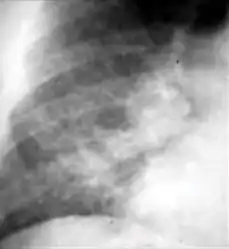

Dense homogenous opacity in right, middle and lower lobe of primary pulmonary TB.

Dense homogenous opacity in right, middle and lower lobe of primary pulmonary TB. Chest x-ray showing patchy opacification on the upper right and mid-zone lung with fibrotic shadows, as well as bilateral hilar lymphadenopathy.